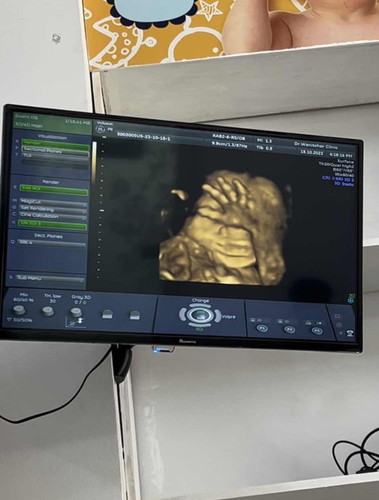

ขอทราบน้ำหนักลูกๆในครรภ์ตอนท้อง 6 เดือนของแม่ๆได้มั้ยคะ เมื่อวานพึ่งไปหาหมอมาค่ะ 24+2 w น้องหนัก 833 กรัม คุณหมอบอก แก้มเยอะมากๆค่ะ ถ้าตามเกณฑ์ จะประมาณ 600 กรัม บ้านนี้เลยไปเยอะเลยค่ะ🥹#ลูกคนแรก

น้องอาจจะมีพัฒนาการทางร่างกายเร็วก็ได้ค่ะ มีความเอามือปิดตาด้วย เอ็นดู💗

ปิดหน้า ปิดหู ทุกครั้งที่ไปซาวด์เลยค่ะ55555

ดูสิมีเอามือปิดหน้าด้วย555รู้เลยคลอดออกมาต้องเป็นเด็กทะเล้นแน่นอน🤣